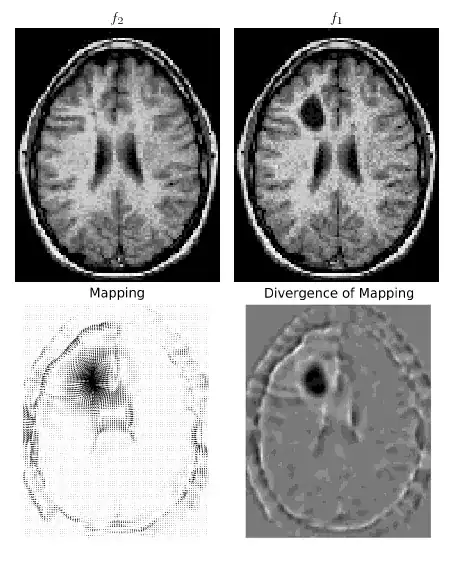

I am implementing the paper "Optimal Mass Transport for Registration and Warping", my goal being to put it online as I just cannot find any eulerian mass transportation code online and this would be interesting at least for the research community in image processing.

The paper can be summarized as follows :

- find an initial map $u$ using 1D histogram matchings along the x and y coordinates

- solve for the fixed point of $u_t = \frac{1}{\mu_0} Du \nabla^\perp\triangle^{-1}div(u^\perp)$ , where $u^\perp$ stands for a 90 degrees counter clockwise rotation, $\triangle^{-1}$ for the solution of the poisson equation with Dirichlet boundary conditions (=0), and $Du$ is the determinant of the Jacobian matrix.